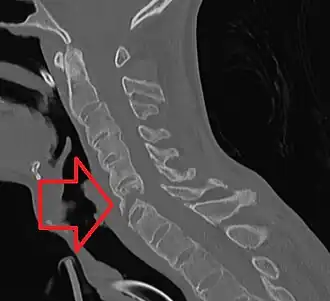

Повреждения нижнего шейного отдела позвоночника

В этой части рассмотрены повреждения, которые чаще всего отмечаются на уровне с C3 до C7 позвонков.